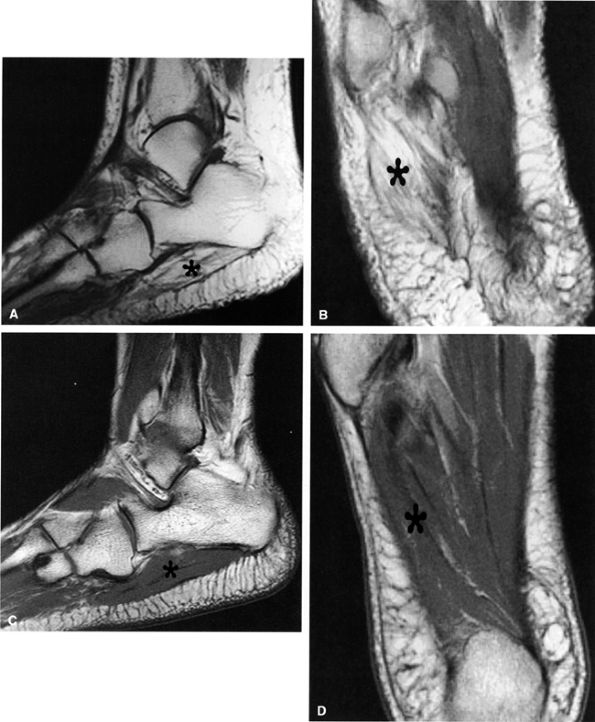

In our experience, incidental MR detection of denervation edema and atrophy of the abductor digiti quinti muscle is not uncommon and most likely reflects a clinically missed entrapment of the first branch of the lateral plantar nerve (Figs. 6.55 and 6.56).

FIGURE 6.56 ● Neuropathy of the inferior calcaneal nerve (Baxter's neuropathy) in a 66-year-old patient with tarsal tunnel varicosities. Sagittal (A) and axial (B) T1-weighted images of the ankle demonstrate denervation atrophy of the abductor digiti quinti muscle (asterisk). (C and D). Normal abductor digiti quinti muscle (asterisk) in an asymptomatic patient for comparison.